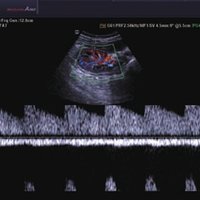

• Farb-Doppler

• Pulsed Wave (PW)-Spektral-Doppler

• Color Opt Flow™ bietet kraftvollere Farben und verbessert die Bildqualität.